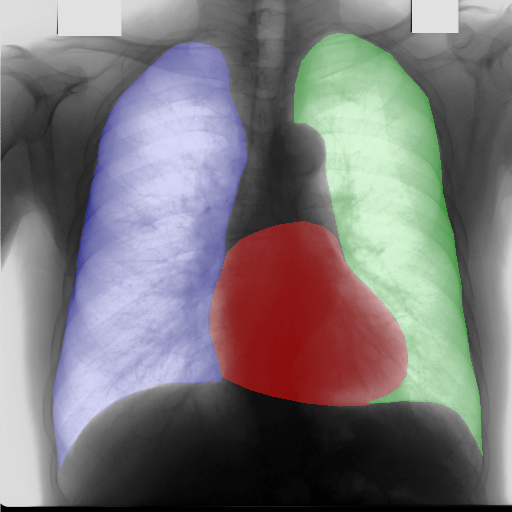

In this section, some examples of images and corresponding segmentations, generated with the approaches described in Section 3, are qualitatively examined. We also report some comments from three physicians on the generated segmentations, to provide a medical assessment of the quality of our method.

Figure 5 and Figure 6 display some examples — randomly chosen from all the generated images — of the label–maps and the corresponding chest X–ray images generated with the three methods described in Section 3, using the FULL_DATASET and the TINY_DATASET, respectively. We can observe that, with the single and two–stage methods, the images tend to be more similar to those belonging to the training set. For example, in most of the generated images there are white rectangles, which resemble those present in the training images, used to cover the names of both the patient and the hospital. Instead, the three–stage method does not produce such artifacts, suggesting that it is less prone to overfitting.

Moreover, in order to clarify the limits of the three–stage method, we assessed the quality of the segmentation results based on three human experts, who were asked to check 20 chest X–ray images, along with the corresponding supervision and the segmentation obtained by the SMANET network. Such images were chosen among those that can be considered difficult, at least based on the high error obtained by the segmentation algorithm. Figure 7 and Figure 8 show different examples of the images evaluated by the experts. The first column represents the chest X–ray image, while the second and the third columns, whose order was randomly exchanged during the presentation to the experts, represent the target segmentation and our prediction, respectively. The three physicians were asked to choose the best segmentation and to comment about their choice. Apart from a general agreement of all the doctors on the good quality of both the target segmentation and the segmentation provided by the three–stage method, surprisingly, they often chose the second one. For the examples in Figure 7, for instance, all the experts share the same opinion, preferring the segmentation obtained by the SMANET over the ground–truth segmentation. To report the results of the qualitative analysis, we numbered the target and predicted segmentation with 1 and 2, respectively, while doctors were assigned unordered pairs to obtain an unbiased result. Then, with respect to Figure 7(a), the comments reported by the experts were: 1) In segmentation 1, a fairly large part of the upper left ventricle is missing; 2) I choose the segmentation number 2 because the heart profile does not protrude to the left of the spine profile; 3) The best is No. 2, the other leaves out a piece of the left free edge of the heart, in the cranial area. Instead, for Figure 7(b), we obtained: 1) The second image is the best for the cardiac profile. For lung profiles, the second image is always better. The only flaw is that it leaks a bit on the right and left costophrenic sinuses. 2) Image 2 is the best, because the lower cardiac margin is lying down and does not protrude from the diaphragmatic dome. Image number 1 has a too flattened profile of the superior cardiac margin. 3) No. 2 for the cardiac profile more faithful to the real contours.